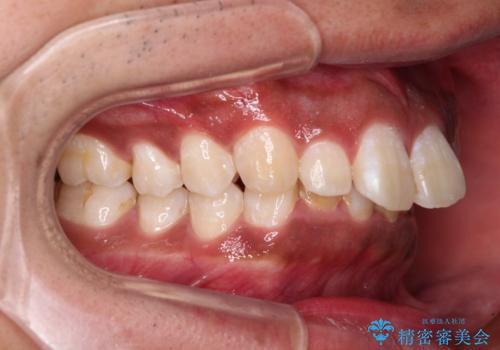

口元の突出感はあまりありませんでしたが、上顎歯列が全体的に前方にあり、更には下顎歯列が深く咬みこんでいるために、上顎前歯が前方に突出している状態でした。

正面や横から見た印象が同じで用であっても、奥歯の咬み合わせが理想的であるかどうかによって、治療の難易度は大きく異なります。